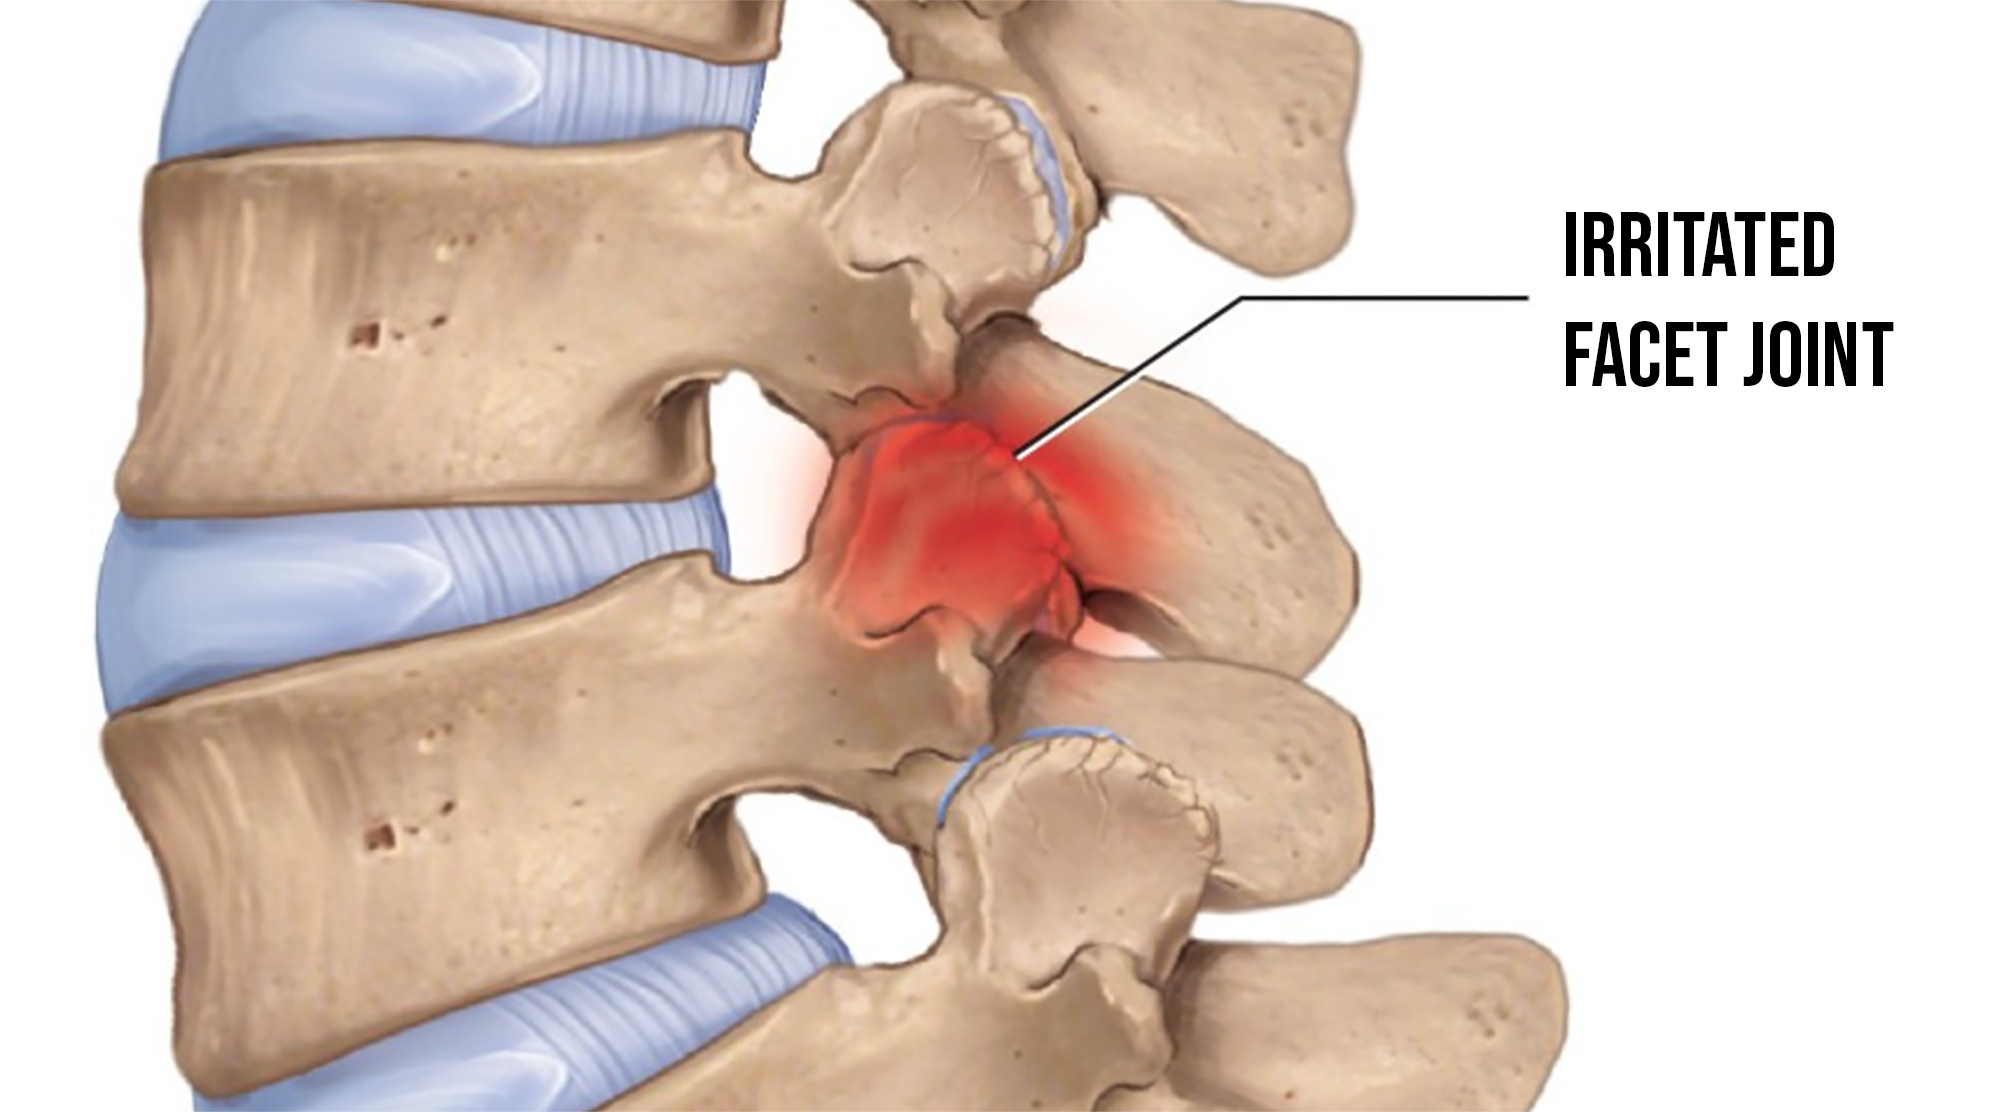

The facet joints are the small joints at the back of the spine. As disc mechanics change, those joints start to take more compressive stress and can develop arthritic changes over time (arthropathy). This is what was visible on Ali's recent MRI.

This is one reason some people get pain with standing, walking or arching. Upright positions often increase load on the facet joints in the posterior part of the spine.